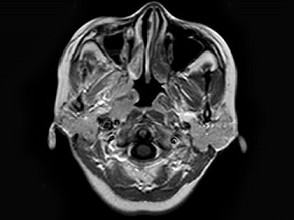

女,34岁。右侧听力下降,耳鸣2个月。MRI平扫及增强扫描如图示,最可能的诊断是 ( ) EBH-00871.jpg EBH-00872.jpg EBH-00873.jpg EBH-00874.jpg

• D.神经源性肿瘤